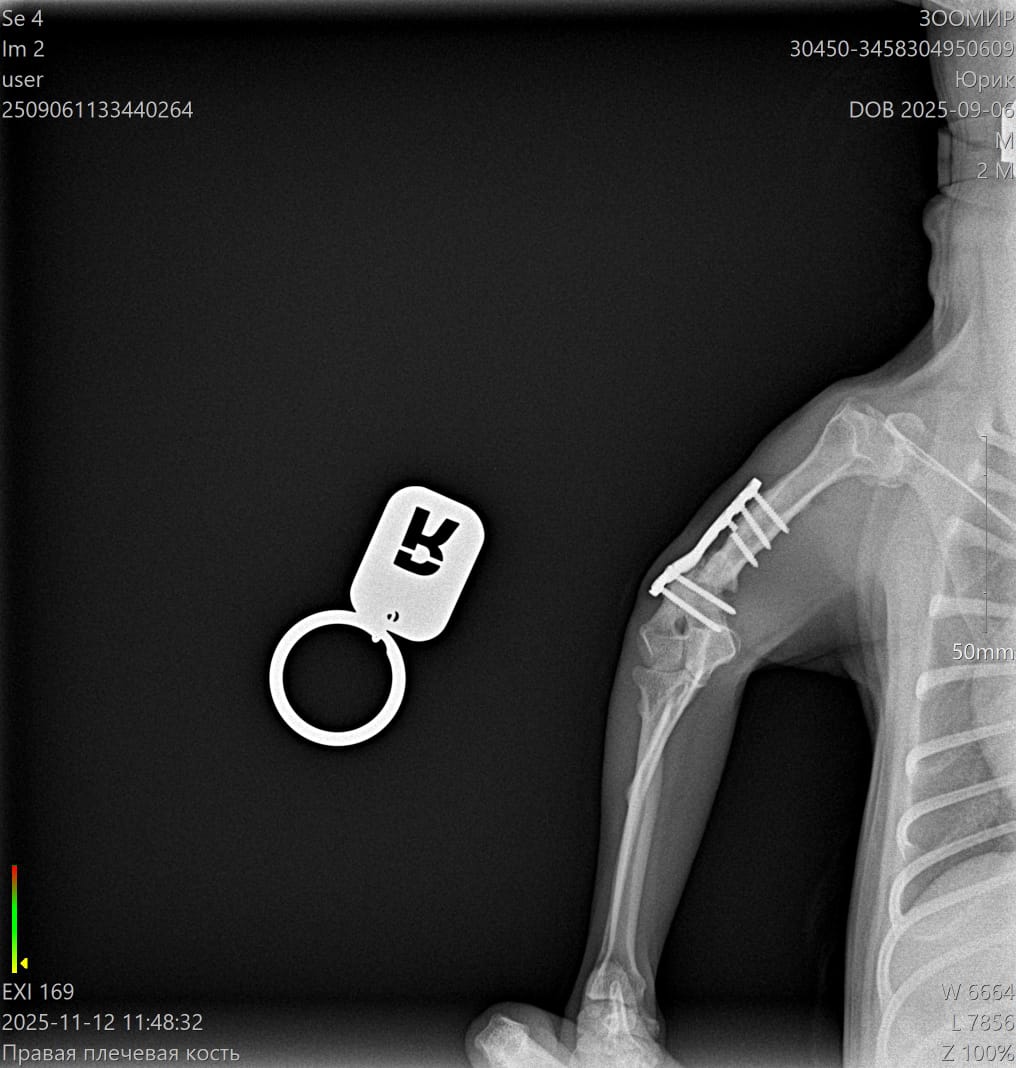

Юрик съездил сегодня на контрольный рентген.

Мозоль ОБРАЗОВАЛАСЬ. По центру она еще не очень плотная, но кость срослась.

Как Ольга паразита не оберегала, но на рентгене оказалась чуть погнутая пластина и один сломанный винт.

Снимать ничего не будем из конструкции, если не начнет отторгаться или двигаться.

2 рентгена и осмотр АН обошлись в 2600₽ ( это стоимось 2 снимков).

Юрик. Взгляд изнутри